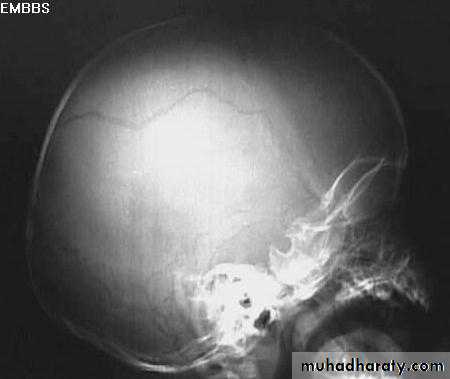

a. Plain skull x-ray

1. Can demonstrate the site and type of a skull fracture.2. A foreign body can also be seen.

Skull Fracture

Indications for skull x-ray in head injury